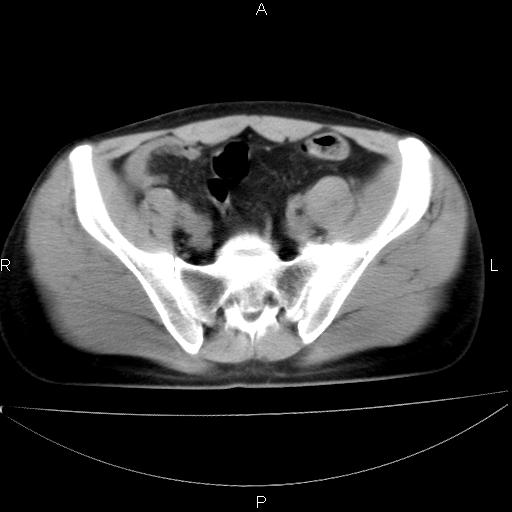

男 25岁 自述 尿频尿急,排尿困难20多天.无腰痛, b超说左肾盂轻度积水,左输尿管上端扩张.未见结石影. ct我看双侧肾盂轻度积水,双输尿管上端都扩张,大家看看能看见结石吗?

双肾轻度积水,双侧输尿管上段扩张(原因待查)。

双输尿管扩张下端未见高密度结石和输尿管晕轮征,不好说是结石.增强后如何?

双肾盂及双输尿上段轻度积水,双输尿管未见明显结石影。